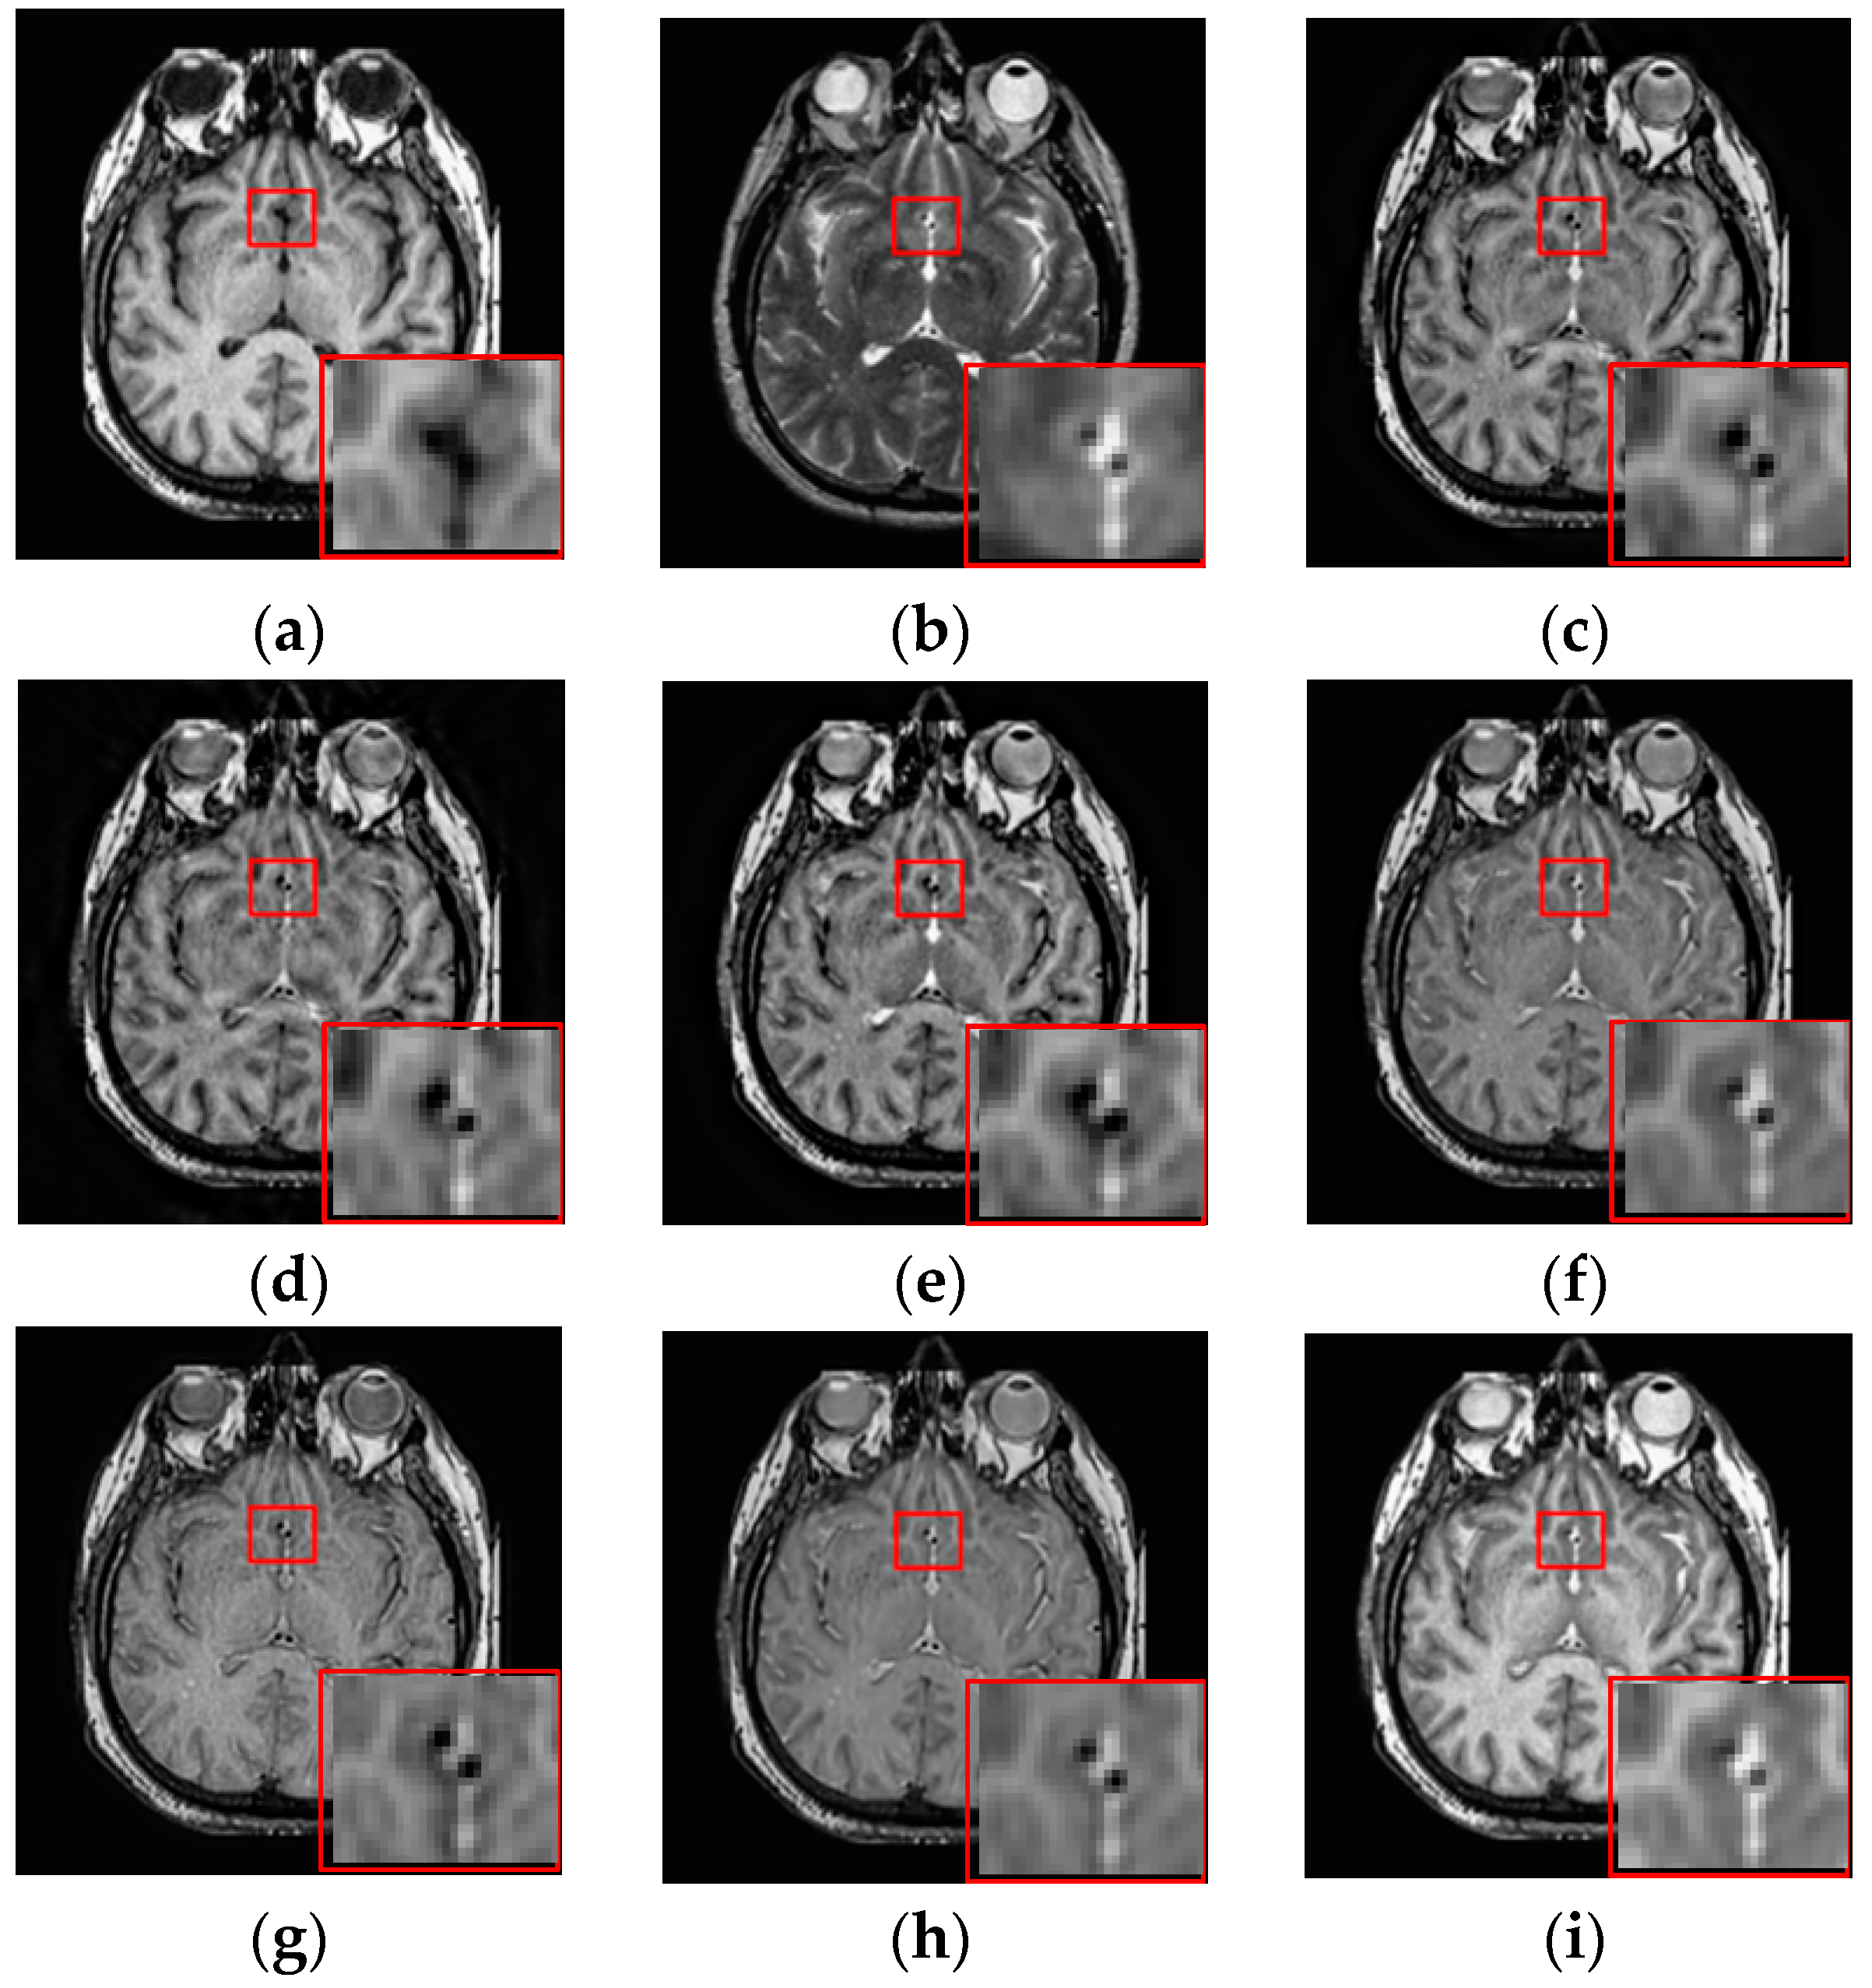

3.3. Fusion Results by Subjective Visual Effects Analysis

The results of the first set of experiments are shown in Figure 7, and the source MRI and CT images are listed in Figure 7a,b. The fused images obtained by the DCTWT, Curvelet, NSCT, Liu-ASR, Kim, Zhu, and the proposed method are displayed in Figure 7c–i, respectively. To facilitate subjective visual comparisons, local regions enclosed by red colored rectangular boxes in Figure 7 are enlarged and presented in the bottom right corners of their respective images. We can notice that the diverse fusion performance generated by different methods in retaining the brightness information and edge detail the information of source medical images. Despite the MST methods expressing source information with different scales and directions, all of the results obtained by DTCWT, Curvelet and NSCT in Figure 7c–e still produce some distortion, which heavily decreases the qualities of the medical images. Meanwhile, after careful observation, we can find the fusion results generated by Liu, Kim and Zhu can preserve details well from MRI. However, the brightness active level is relatively lower than the source CT image, which indicates the loss of useful information. It can be seen from Figure 7i that the fusion result obtained by the proposed method has the best performance in terms of retaining brightness information and detail information, which indicates that the visual effect of the method is the best.

Figure 7.

Fused results of MRI/CT medical images by different methods. (a) MRI; (b) CT; (c) DCTWT; (d) Curvelet; (e) NSCT; (f) Liu-ASR; (g) Kim; (h) Zhu; (i) Proposed.

The fusion results of different methods about “MR-T1/MR-T2” (see Figure 8a,b) are shown in Figure 8c–i. For this experiment, the detail information (shape, edge, texture et. al) in the red rectangle is mainly from the MR-T1 image while the energy information (brightness, contrast et.al) mainly from MR-T2 image. Among these fusion results, it can be seen that the details of the fusion results produced by the DTCWT, Curvelet and NSCT methods are severely damaged, especially the Curvelet method. Although the Liu-ASR, Kim and Zhu methods can relatively effectively protect the edge details of the source image, they do not protect the contrast of the image well. This is very disadvantageous for medical images with high-quality requirements, and is not conducive to subsequent medical image processing and recognition tasks.

Figure 8.

Fused results of MR-T1/MR-T2 medical images by different methods. (a) MR-T1; (b) MR-T2; (c) DCTWT; (d) Curvelet; (e) NSCT; (f) Liu-ASR; (g) Kim; (h) Zhu; (i) Proposed.

By comparison, our fusion result (Figure 8i) can not only effectively protect the edge detail information of the source image, but also maintain the contrast of the source image, which is mainly due to the detail enhancement processing of training set and the clustering techniques to classify brightness and detail groups before dictionary learning. At the same time, little artificial false information is introduced in our fusion result, which means that the visual effect of the proposed method outperforms others methods in this experiment.